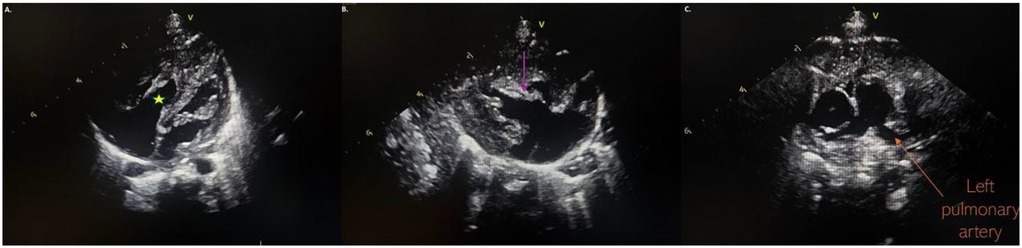

At our hospital, the physical examination was unremarkable. Echocardiography displayed an undeveloped trabecular part of the right ventricle (RV) with a small cavity and prominent papillary muscles (Figure 1A), patent foramen ovale (PFO) with bidirectional, predominantly left to right shunt and mild tricuspid valve regurgitation (peak pressure gradient 45 mmHg), as well as insignificant regurgitation on the mitral valve. Left pulmonary artery (LPA) blood flow was laminar with a velocity of 1.6 m/s (Figure 1). The flow in patent ductus arteriosus (PDA) was not identified. Based on these findings, a diagnosis of IRVH was made, and further monitoring was advised.

Figure 1. (A) Hypertrabecular right ventricle with a small cavity (yellow star); (B) massive hyperechogenic tricuspid papillary muscle (purple arrow); (C) normal pulmonary artery without pathological masses.